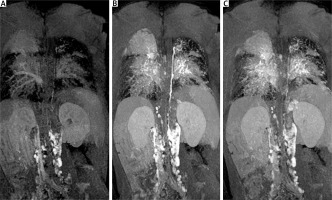

Cardiac catheterisation revealed a significant collateral vessel from the left inferior thyroid artery supplying the left lung and additional collateral vessels arising from the left (LIMA) and right (RIMA) internal mammary arteries supplying both lungs (Figure 1). The Fontan tunnel measured 14.1 mm at its junction with the IVC, widening centrally to 26 mm, and tapering to 10.9 mm at the junction with the pulmonary arteries. No fenestration was identified. The stent in the left pulmonary artery measured 9.8 mm proximally, increasing to 11.2 mm distally (Figure 2). During the procedure, an Amplatzer Vascular Plug successfully occluded the collateral vessel from the left inferior thyroid artery to the left lung, and vascular coils were placed in the RIMA and LIMA. Additionally, a 6-mm Valeo stent was implanted to create a new fenestration (Figure 3).

Figure 1

Angiogram of the left brachio-cephalic vein. The plug is inserted into the left mammary artery. Wide left brachio-cephalic artery (innominate artery), and the collateral vessel to the left lung (asterisk) are visible. A stent was placed in the left pulmonary artery